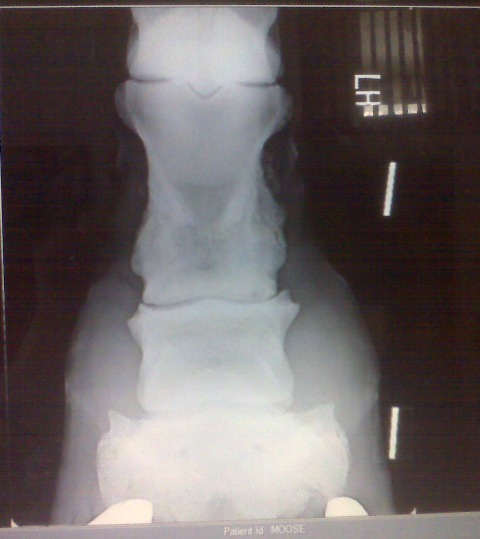

Posted on Sunday, Jun 27, 2010 - 10:00 am: Here are his x-rays that were taken 9/2007. It looks like references I have looked up as ringbone, what do you think?![]() ![]() ![]()

Posted on Tuesday, Jun 29, 2010 - 1:45 pm: Talk about a picture being worth a thousands words! Melissa your horse is not suffering so much from sidebone but has ringbone. This is a periostitis of the bones of the pastern that is spreading into the pastern joint (osteoarthritis) as evidenced by the osteophytes on the distal long pastern bone and proximal short pastern bone. By all means review the article on ringbone at HorseAdvice.com » Diseases of Horses » Lameness » Diseases of the Lower Limb » Ringbone. If you have questions following the article come back you can post them there and I will move this discussion into your post for continuities sake.DrO |